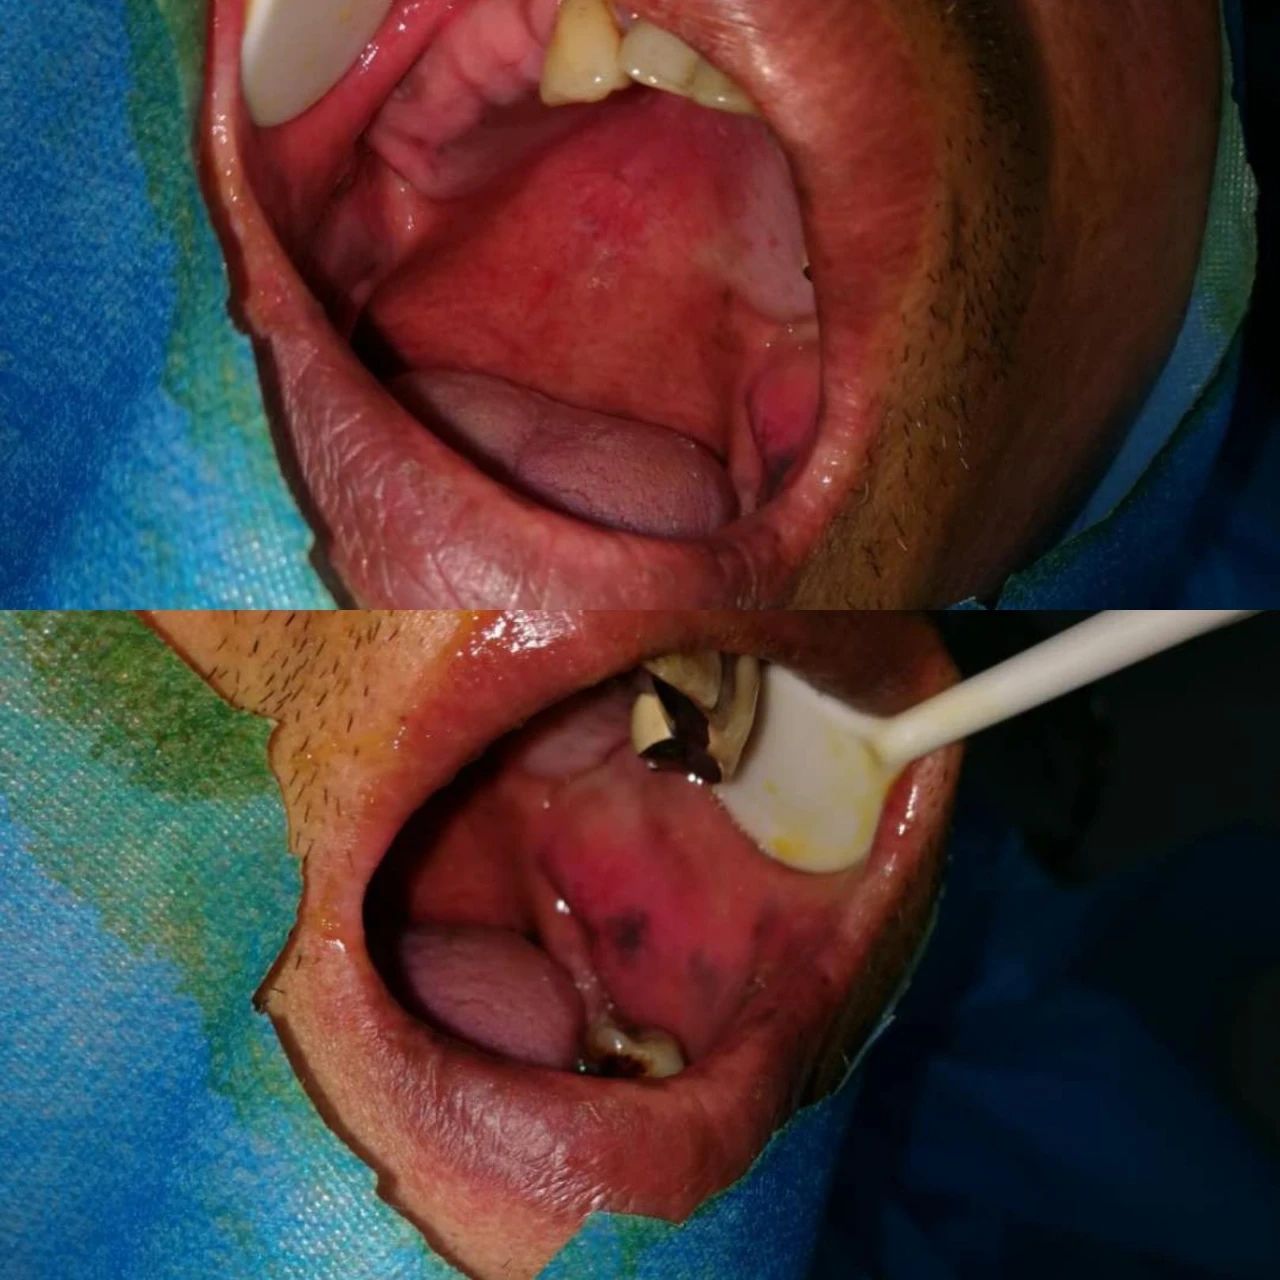

此次培訓(xùn)由美國(guó)哈佛大學(xué)牙學(xué)院博士張杰發(fā)起,江陰金泰克生物技術(shù)有限公司舉辦的。張杰博士和山西省口腔醫(yī)學(xué)會(huì)副會(huì)長(zhǎng)鄭強(qiáng)教授、金泰克旗下門診醫(yī)師張乙云共同為學(xué)員們呈現(xiàn)了一場(chǎng)精彩的口腔學(xué)術(shù)盛宴。種植技術(shù)示范現(xiàn)場(chǎng),鄭強(qiáng)教授和張乙云醫(yī)師一小時(shí)內(nèi)為患者種植牙15顆,現(xiàn)場(chǎng)觀摩學(xué)員無(wú)不對(duì)金泰克種植體系統(tǒng)先進(jìn)的設(shè)計(jì)原理和簡(jiǎn)易的操作方法表示稱贊。

學(xué)員現(xiàn)場(chǎng)觀摩鄭強(qiáng)教授手術(shù)示范,一小時(shí)內(nèi)完成15顆種植牙

手術(shù)過(guò)程時(shí)間持續(xù)一個(gè)小時(shí),患者缺失的主要為后牙部分,情況復(fù)雜,難度較高,術(shù)后無(wú)不適狀況,面部無(wú)腫痛。